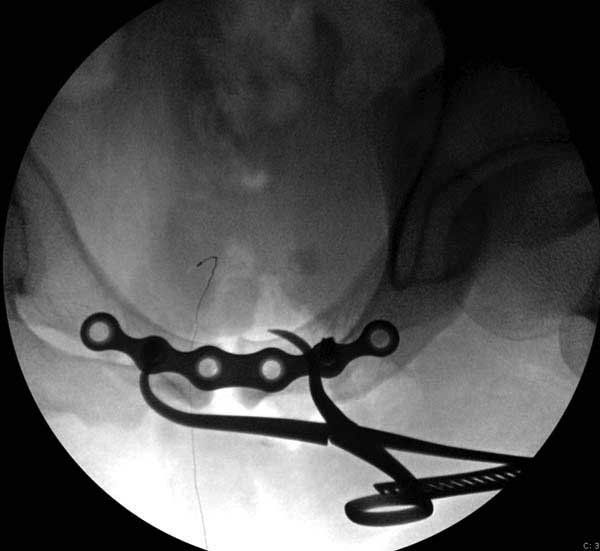

Здесь представлен случай 38 летнего больного (падение с высоты 9 метров) с нарушением тазового кольца. При поступлении для стабилизации передне-нижний аппарат наружной фиксации и на 6й день, вчера, операция из двух доступов.

Представлены снимки техники проведения стержней. Через место прикрепления прямой мышцы в Inferior Iliac Spine в направления вырезки создается жесткость. Weber clamp изнутри таза для репозиции, и фиксация после репозиции перелома крыла подвздошной кости. Наружный аппарат удален, нагрузка предполагается через два месяца.